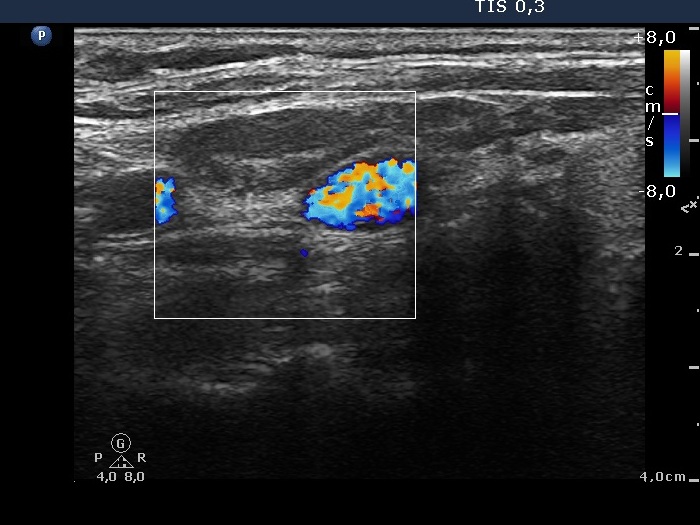

Lymph nodes - case 73 (ultrasonographic picture 6)

Left side of the neck, above the thyroid, longitudinal scan, color Doppler mode. There is no vascularization according to the lymph node.